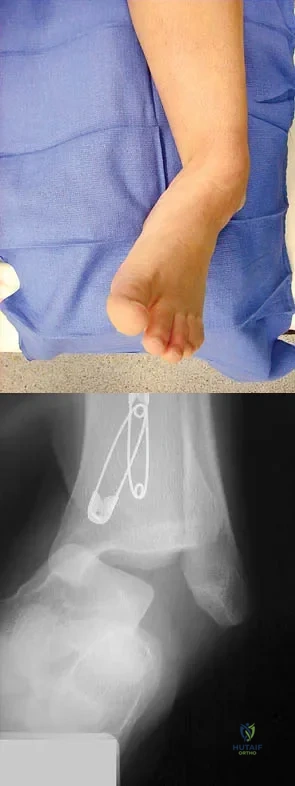

An 11-year-old boy has had a fever and pain and swelling over the lateral aspect of his right ankle for the past 3 days. Examination reveals warmth, swelling, and tenderness over the lateral malleolus, and he has a temperature of 103.2 degrees F (39.5 degrees C). Laboratory studies show a WBC count of 13,200/mm3 with 61% neutrophils, an erythocyte sedimentation rate of 112 mm/h, and a C-reactive protein of 15.7. Radiographs and a T2-weighted MRI scan are shown in Figures 13a through 13c. Aspiration yields 1 mL of purulent fluid. Management should now consist of

A 15-year-old boy with a type I hereditary sensory motor neuropathy (Charcot-Marie-Tooth disease) reports recurrent ankle sprains and significant pain in the hindfoot and midfoot despite orthotic management. Examination reveals that he walks with a drop foot and has dynamic clawing of the toes. Clinical photographs of the left foot are shown in Figure 7. Management should consist of